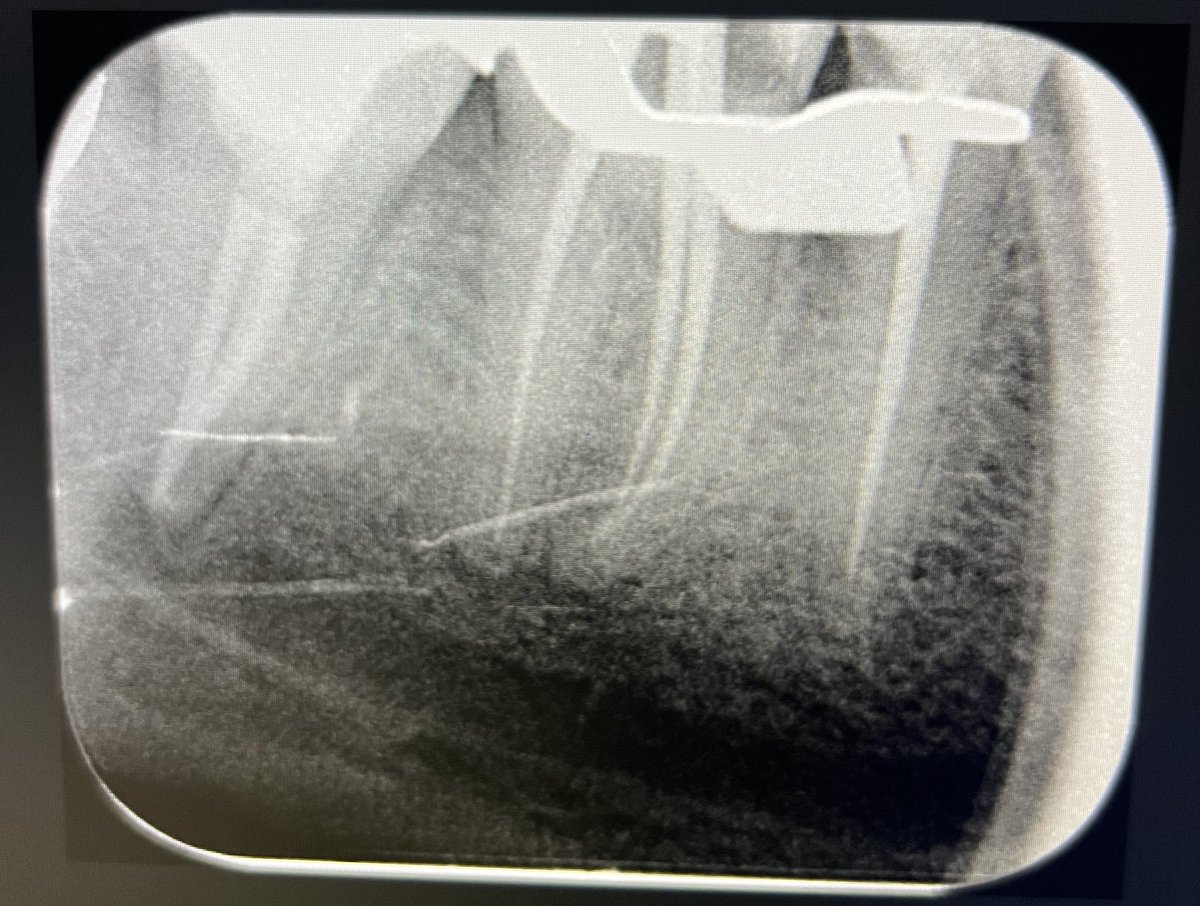

Today’s case:

Rct of #11 Dx : PI/AAA

• 1st visit: Open access, irrigation, abscess drainage, and dressing the canal with Ca(OH)₂.

• 2nd visit (after 30 days): Reopening the tooth, irrigation performed; the canal was completely dry and ready for obturation.

Patient is fine😁